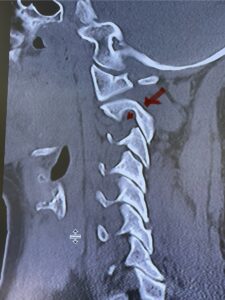

Cervical x-rays revealed a significantly increased atlanto-axial interval (Fig. 5) On review of her imaging studies it was noted that the right C2 isthmus was very thinned by the vertebral foramen (Figs 6a, b, and c) which would make an attempt at placing a C2 pars screw dangerous. A decision was made to perform an occipital-cervical fusion because only possible unilateral fixation and an extensive C1 laminectomy to be performed eliminating a fixation point if a more traditional C1-C2 was performed. Even if C1 lateral mass screws were able to be placed one could only perform a unilateral screw construct fixation to C2. We performed an occipital cervical fusion down to C4 to get enough inferior fixation and C1 laminectomy. The decompression went well. We placed a left unilateral pars screw and bilateral C3 and C4 lateral mass screws. We placed three 12 mm screws in the midline keel (Fig. 7). Postoperatively the patient had all around improvement in her symptoms and did not qualify for rehab. Her post op films at 6 weeks (Fig. 8)

Fig. 6a: Sagittal cervical CT scan demonstrating an abnormally thin right C2 isthmus prohibiting safe placement of screw (red arrow). Notice the vertebral foramen eroding the isthmus bone structure (red dot).